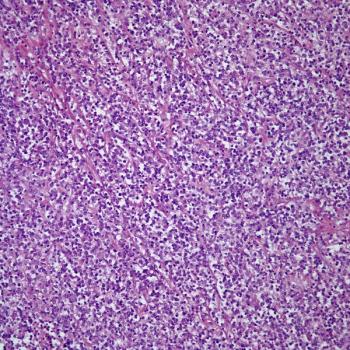

An otherwise healthy 38-year-old man presents with an enlarged lymph node in the right side of the neck. Surgical resection of the lymph node is performed. What is your diagnosis?